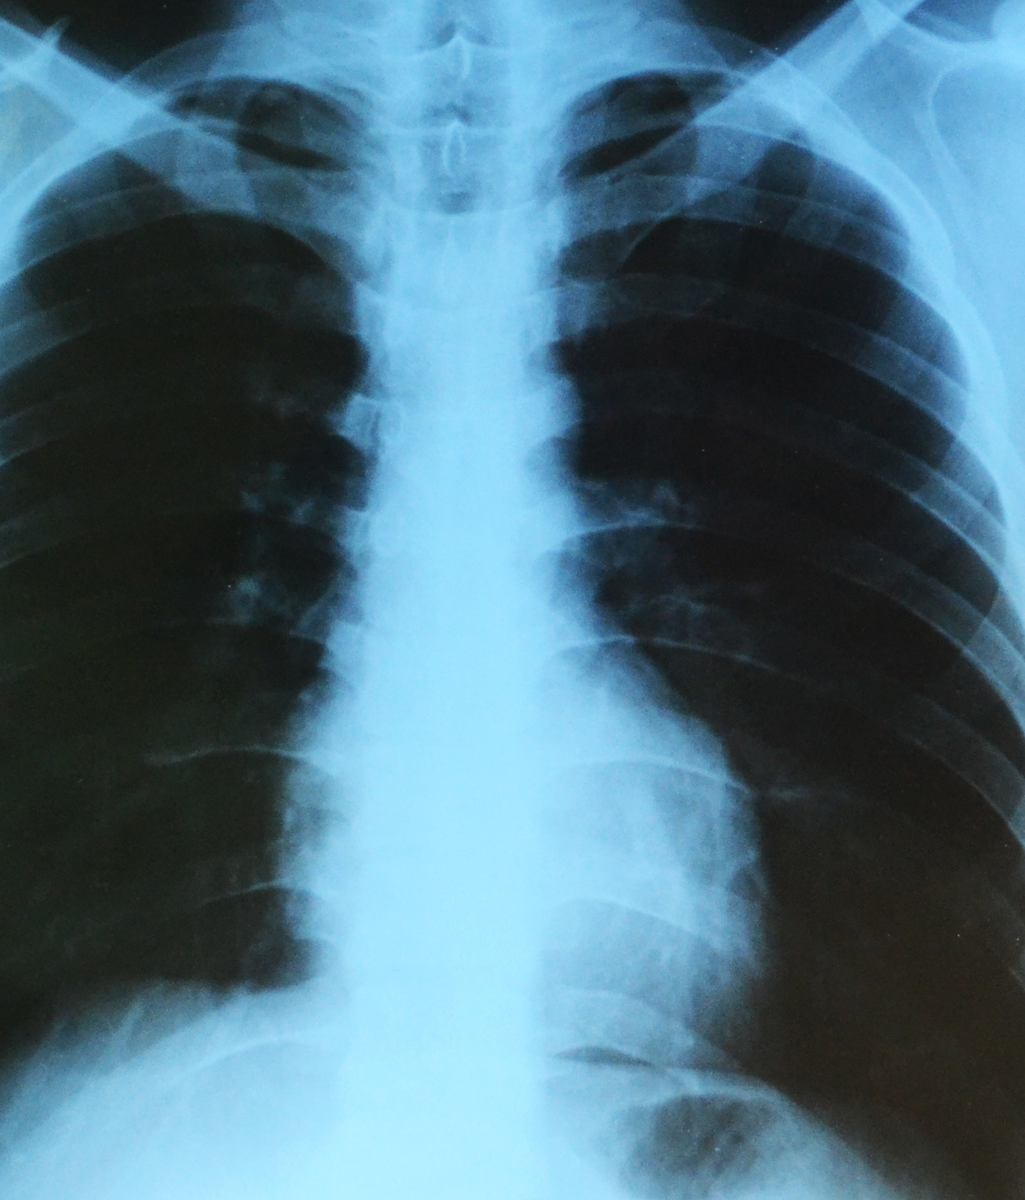

Les examens radiographiques font partie des procédures médicales standard depuis de nombreuses décennies. Ils servent à confirmer une suspicion de maladie, à examiner le cœur et les poumons, à détecter des tumeurs ou à rendre visibles les occlusions vasculaires.

La radiographie est une méthode d'examen dans laquelle un corps est irradié avec un rayonnement radiographique et, par conséquent, une image de ce rayonnement est produite. Dans le passé, ces images étaient enregistrées sur du matériel de film. Aujourd'hui, cela est également possible par voie électronique.

Les rayons X qui traversent le corps sont plus ou moins fortement "absorbés" (absorbés) en fonction du type de tissu. Un os transmet moins de radiations, un autre muscle. Dans la radiographie d'un bras, nous voyons donc l'os comme une structure blanche, le muscle comme une structure sombre.